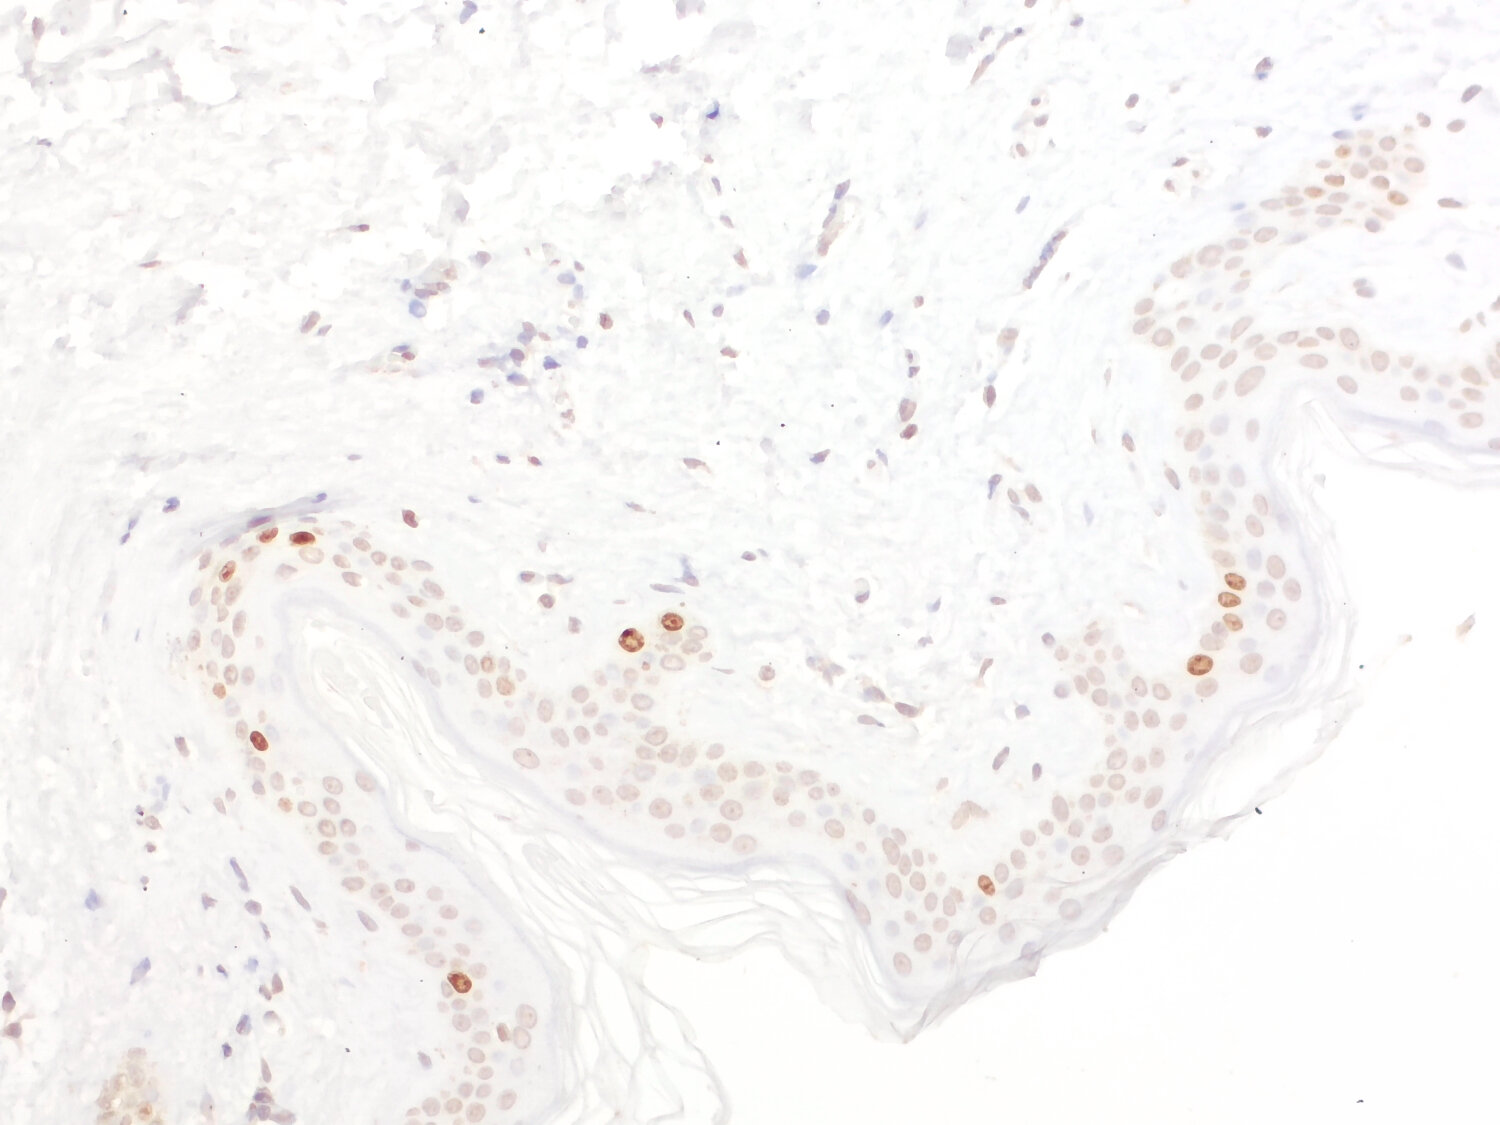

Detection of proliferation antigen Ki-67 in human colon cancer

Expression of the nuclear protein Ki 67 is strictly associated with cell proliferation and preferentially expressed during the late G1, S, G2 and M phases of the cell cycle. Resting cells (G0 phase) lack Ki 67 expression .

Immunohistochemical detection of Ki 67 is a simple and reproducible method to determine the tumour proliferative index and is a predictive and prognostic biomarker in certain types of human cancer, such as breast cancer, gastric cancer or prostate cancer. Moreover, higher Ki 67 scores may be associated with increased tumor sensitivity to radiation therapy and chemotherapy.

IP: not tested yet ICC: not tested yet IHC: not tested yet IHC-P: 1 : 2000 gallery |